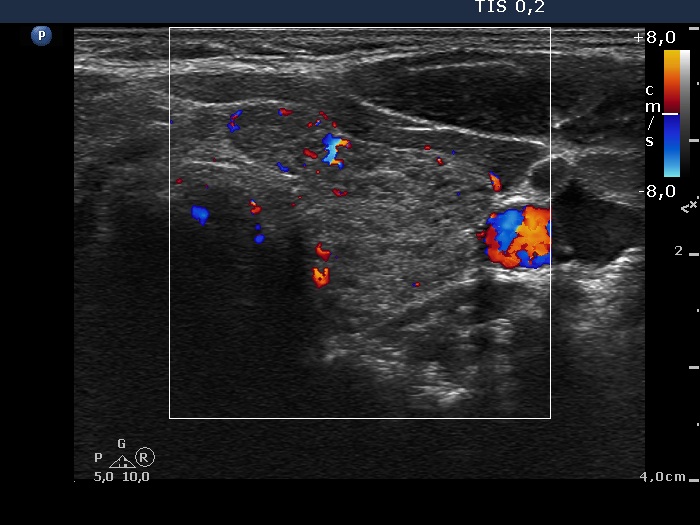

Left lobe, transverse view, color Doppler mode. The vascularization is not specific.